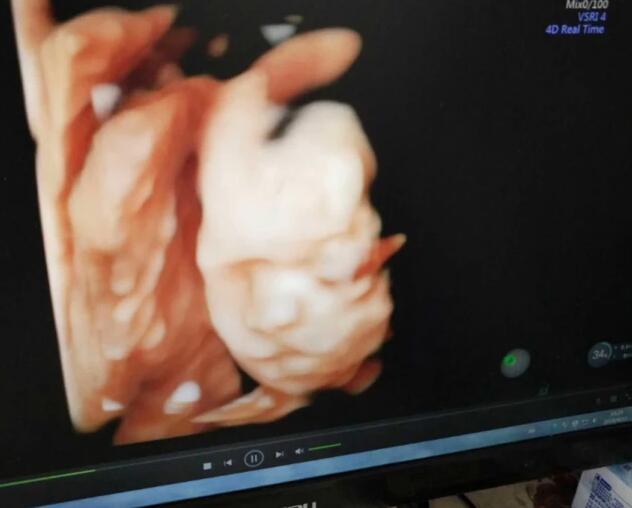

孕妇在怀孕的时候,早期孕检做的是普通的彩超。等到孕妇到孕后期的时候,到医院孕检的时候就会做四维彩超。这个四维彩超主要是为了检查孩子会不会畸形或者是残疾。检查孩子的脊柱、脑袋、四肢的情况。但是孩子还没有发育完全,所以四维彩超图可能会很丑。

四维彩超图片是多角度考声波合成图片,来供医生判断胎儿发育的情况。所以医生会用检测仪在孕妇肚子上来回滑动,多个角度的来观察孩子的情况,加上孩子是在羊水中,所以照片出来会和孩子真实的相貌大不相同。我们平时合成的照片都会比较丑,更何况是四维彩超探测肚子里宝宝而合成的照片了。

在孕后期的时候,胎动是非常频繁的,所以很多孕妇在做四维彩超的时候,宝宝在妈妈的肚子里还在活动,这也会影响到最终四维彩超的成像图。